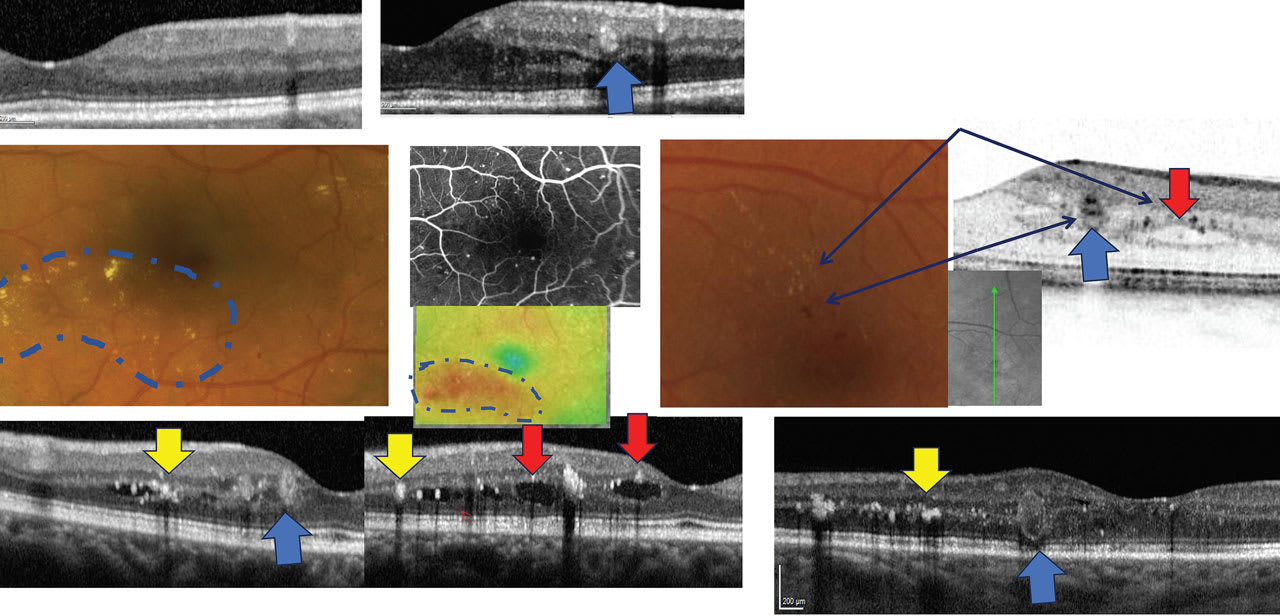

OCT can aid in the identification of the earliest sign of DR: microaneurysms (MAs). They appear as small, distinct, oval-shaped, hyperreflective, walled structures, and are associated with microvascular damage. Specifically, the structural weakness of the vessel wall of MAs causes fluid leakage, resulting in edema. Edema on cross-sectional OCT can be seen as localized hyporeflective cystic-type spaces or diffused areas of retinal thickening, which in the macular region is called macular edema. Chronic edema then results in the accumulation of hard exudates, which is seen as intense hyperreflective deposits with varying amount and intensity within intraretinal layers.

Note the progression of the MA (A) to macular edema (bottom) shown in this structural scan. Center-involved macular edema is seen in the cross-section (B) vs. topography (C). OCT’s imaging of macular edema has resulted in a change of terminology from “clinically significant macular edema (CSME)” to “center-involved” vs. “non-center involved” diabetic macular edema, which includes the central subfield zone. This is defined as the 1000 µm diameter from the foveal center.

Another sequelae of MA formation is progression to intraretinal hemorrhages (IRH), often referred to as “dot-blot” hemorrhages. An intraretinal blot hemorrhage has developed in the foveal area, seen as a large hyperreflective mass; the resolution can be seen to the right. On OCT cross section, IRH can be seen as hyperreflective foci that have varying opacification. The closure of MAs, capillaries, and arterioles results in ischemic changes usually seen as thinning of the inner retinal structures, such as the retinal nerve fiber layer (RNFL) and ganglion cell layer (GCL). This can present in different scenarios. One mechanism is the acute ischemic events clinically seen as localized areas of retinal whitening termed “cotton-wool spots” (CWS). An acute phase of cotton-wool spot is seen resulting in a localized area of retinal whitening and hyperreflectance and thickening of the inner retinal layers on OCT. On OCT cross section, CWS are seen as localized areas of inner retinal thickening and hyperreflectance. Once they disappear clinically, the area noted before demonstrates loss of RNFL and GCL. (The average timeline for this process is a separate management discussion.) Chronic ischemic changes can be seen. Particularly in the macular edema, inner retina atrophy is evident on the cross section. Areas of retinal thinning can also be seen on thickness maps.